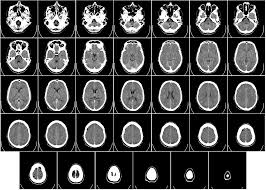

- TAC: otra técnica usa el poder de penetración de los rayos X combinados con la posibilidad de tratar muchos datos de los ordenadores, esto es el TAC (tomografía axial computerizada) y con esto lo que se consigue es dividir los segmentos del cuerpo y permite detectar anomalías anatómicas sin penetras el cuerpo.